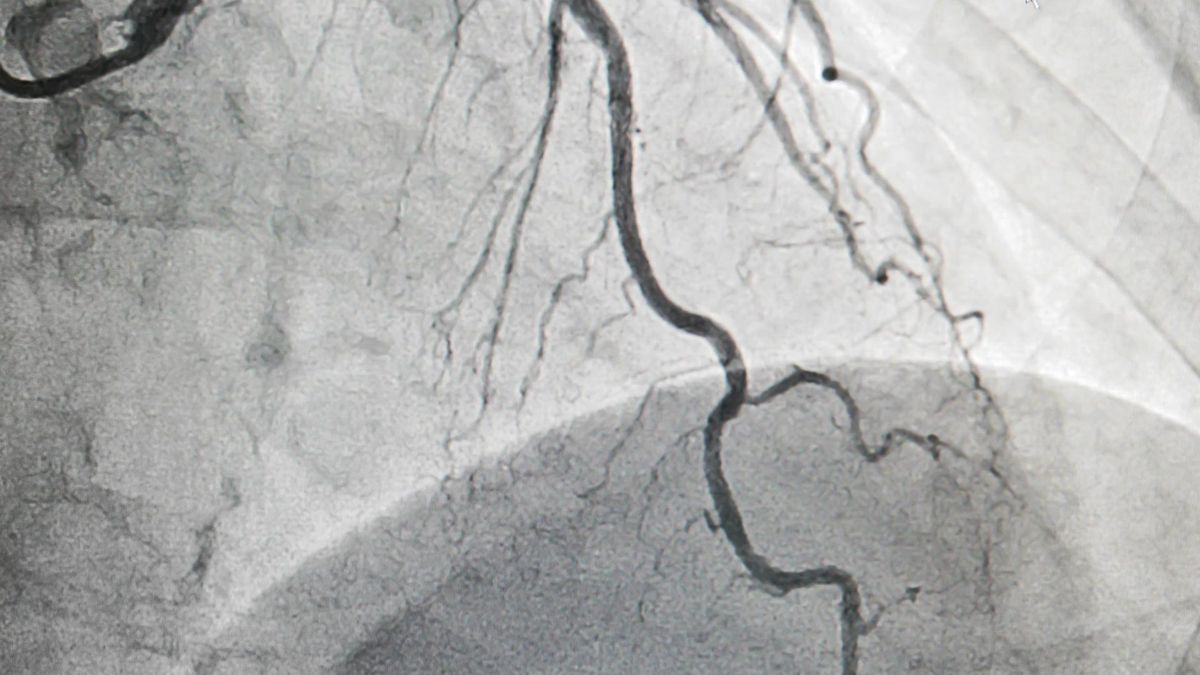

Większość panów wiąże zaburzenia erekcji ze swoim wiekiem. Sądzą, że w życiu każdego mężczyzny przychodzi moment, w którym nie stają już na wysoki zadania w sypialni. Tymczasem zaburzenia erekcji mogą świadczyć o znacznie poważniejszym problemie – chorobie wieńcowej. Zatkane tętnice znajdujące się w miednicy mogą objawiać się niemożnością osiągnięcia erekcji.

Do zaburzeń erekcji dochodzi najczęściej już na 3 do 5 lat przed zawałem serca. Jeśli więc zauważyłeś ostatnio, że coraz częściej seks kończy się jedynie na pragnieniu, czas odwiedzić lekarza. Być może odpowiednia dieta i zmiana stylu życia sprawią, że ryzyko poważnej choroby serca spadnie.